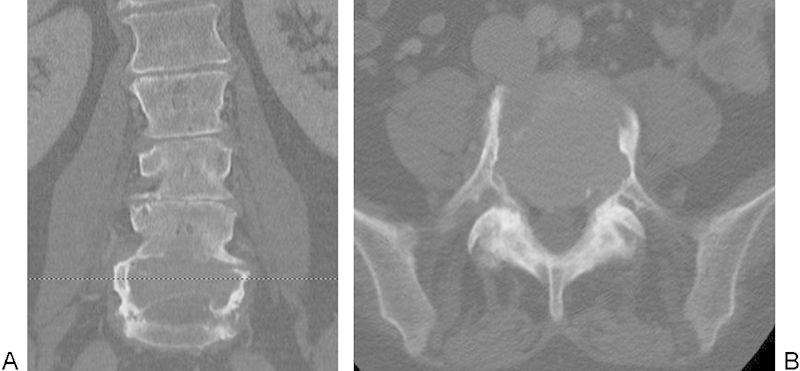

研究设计个案报告及文献回顾。目的:我们在L4和L5行两节段腰椎切除术,以实现巨细胞瘤(GCT)的整体切除和腰骨盆重建。方法一名58岁的女性,有7个月的进行性顽固性背痛和腿部疼痛史,继发于活检证实的L4和L5椎体Enneking III期GCT。患者在两个手术阶段成功接受了L4-L5椎体切除和前后联合入路腰骨盆重建。结果术后并发症包括深部伤口感染和脑脊液漏;然而,在手术清创和长期抗生素治疗后,患者神经功能完好,疼痛最小,随访2年以上无肿瘤复发或器械失效的证据。结论椎体切除术是治疗Enneking III期gct累及下腰椎的一种可行且有效的治疗方法。腰骶交界处是脊柱切除后重建的一个具有挑战性的解剖位置,具有独特的技术考虑。

Study Design Case report and review of the literature. Objective We present the case of a two-level lumbar spondylectomy at L4 and L5 for en bloc resection of a giant cell tumor (GCT) and lumbopelvic reconstruction. Methods A 58-year-old woman presented with a 7-month history of progressive intractable back and leg pain secondary to a biopsy-proven Enneking stage III GCT of the L4 and L5 vertebrae. The patient underwent a successful L4-L5 spondylectomy and lumbopelvic reconstruction using a combined posterior and anterior approach over two operative stages. Results Postoperative complications included a deep wound infection and a cerebrospinal fluid leak; however, following surgical debridement and long-term antibiotic treatment, the patient was neurologically intact with minimal pain and there was no evidence of tumor recurrence or instrumentation failure at more than 2 years of follow-up. Conclusion Spondylectomy that achieves en bloc resection is a viable and effective treatment option that can be curative for Enneking stage III GCTs involving the lower lumbar spine. The lumbosacral junction represents a challenging anatomic location for spinal reconstruction after spondylectomy with unique technical considerations.